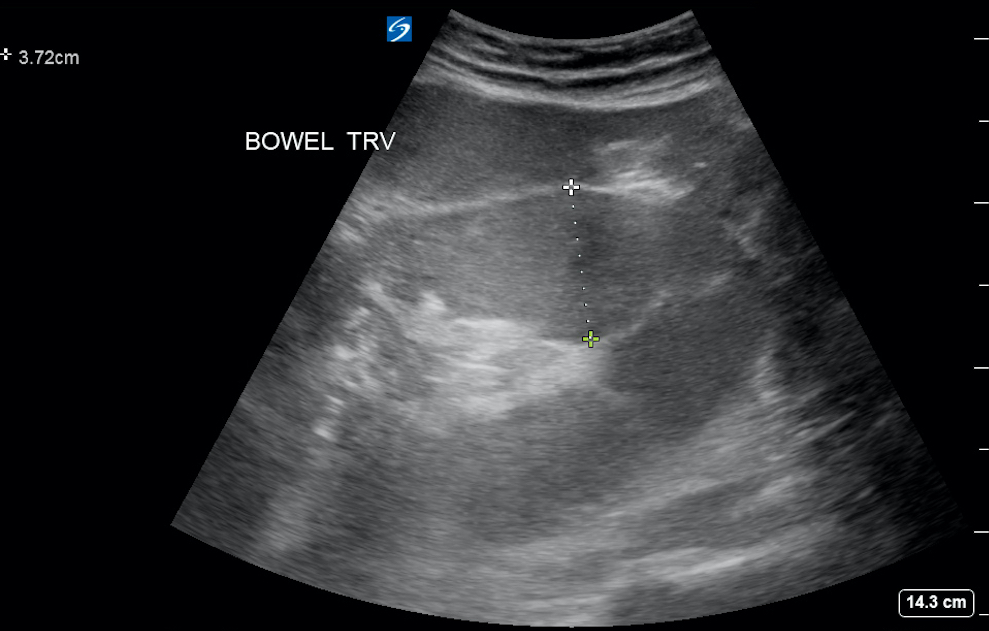

- The diagnosis of SBO is additive. Pathologic findings include dilation of small bowel > 2.5 cm (see Fig. 1), abnormal (“to and fro”) peristalsis (see Video 2), bowel wall thickening, and the presence of extraluminal free fluid between loops of bowel (see Video 3).

- Figure 2. Dilated small bowel in setting of SBO